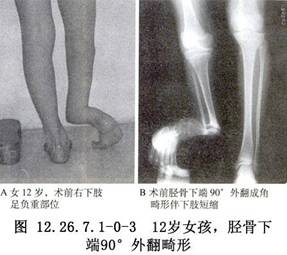

Williams髓内棒插入和植骨术用于先天性胫骨假关节的手术治疗。 先天性胫骨假关节是出生时已经存在或出生时开始出现的一种特殊的骨不连接,其发生原因尚不清楚,但罹患神经纤维瘤病,或与其有相关的一些特征者,发生先天性胫骨假关节的机会明显增加,提示神经纤维瘤病即使不是先天性胫骨假关节的病因,也与先天性胫骨假关节有着密切联系。先天性胫骨假关节最常累及胫骨的远端1/2(图12.26.7.1-0-1~12.26.7.1-0-3)。